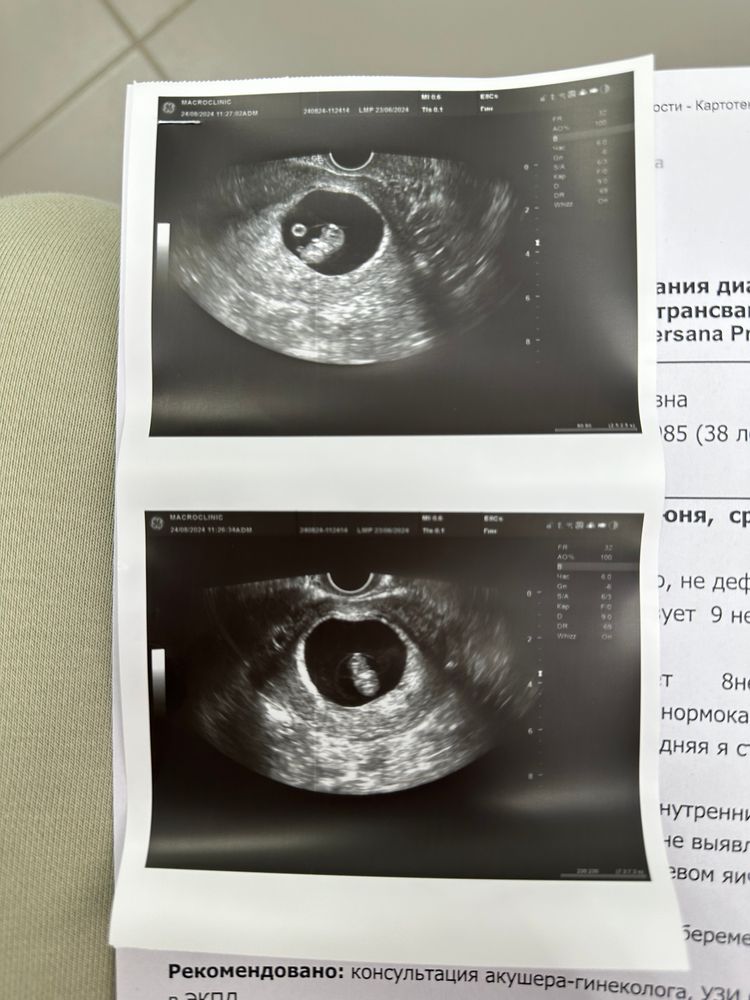

УЗИ почти 9 недель

Результаты УЗИВчера была на узи, показали малявку, все в порядке 😍 Она даже ручками ножками чего то там шевелит уже😍😍😍

Девочки, плодное яйцо опережает по размеру на неделю, это же ничего страшного? Такой манеж у нее😂😍